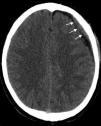

Trombosis de los senos durales. La trombosis del seno longitudinal superior (flechas largas en a y b) y del seno recto (flechas cortas en a y b) evidencia imágenes (a) hiperdensas en la TC e (b) hipointensas en la secuencia GRE en corte axial. (c) La angio-RM venosa TOF, en corte sagital, muestra una señal disminuida en el seno longitudinal superior (puntas de flecha) y ausente en el seno recto-vena de Galeno (asterisco).